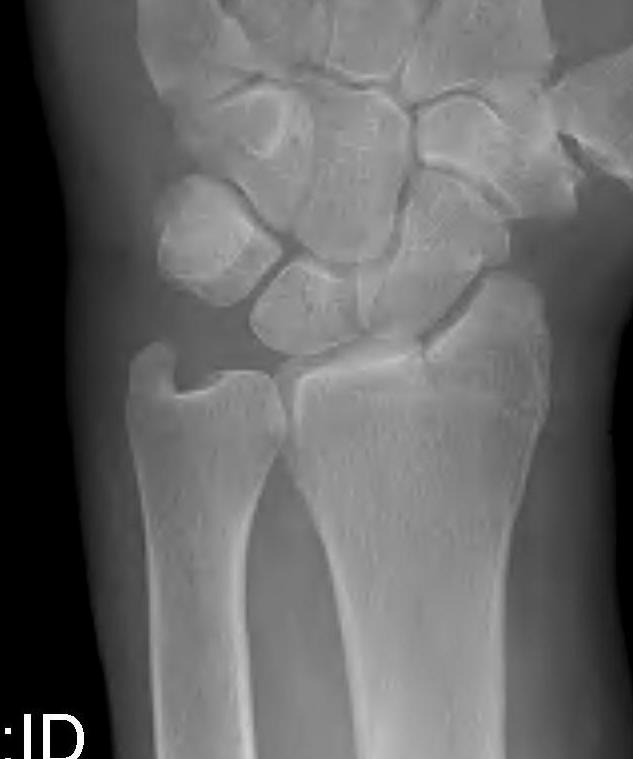

Distal Radius Angles

- radial volar tilt 11°

- radial inclination  22°

- radius is 11 mm longer than ulna

- ulna variance 2mm positive on average

Distal Radius NormalNormal Radial InclinationNormal Radial Length